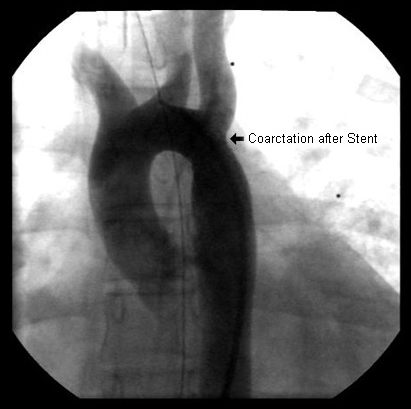

Cardiac catheterisation is not typically necessary for diagnosing aortic coarctation. While direct measurement of the gradient across the aortic coarctation is obtained with cardiac catheterisation, this is usually performed with the intention to intervene and repair a coarcted segment, either by balloon angioplasty or stent expansion.[19][Figure caption and citation for the preceding image starts]: Angiography in the ascending aorta shows a focal area of narrowing after the left subclavian arteryFrom the personal collection of Jeffrey Gossett, MD, Children's Memorial Hospital, Northwestern University, Chicago; used with permission [Citation ends].

[Figure caption and citation for the preceding image starts]: After stent placement the narrowed area is markedly improvedFrom the personal collection of Jeffrey Gossett, MD, Children's Memorial Hospital, Northwestern University, Chicago; used with permission [Citation ends].